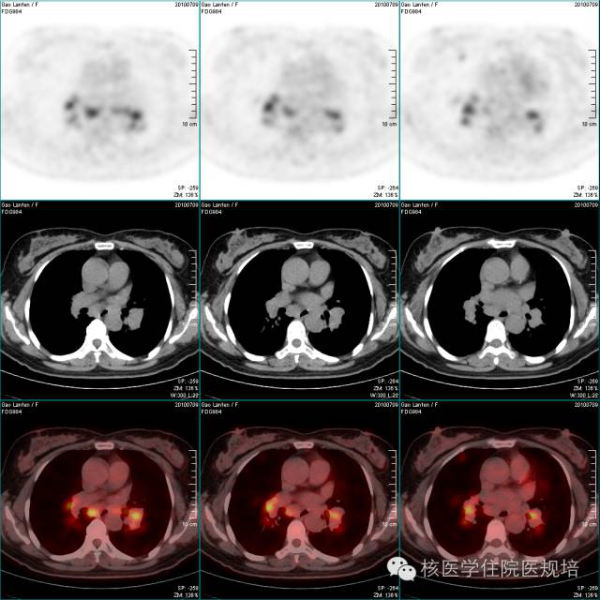

3 示纵隔及双侧腋窝多发淋巴结肿大并放射性异常浓聚

双颈部(图2)、双侧锁骨区、纵隔(图3)、双肺门、双侧胸肌间、双侧腋窝(图3)、右前肋膈角、双膈肌下、腹腔内、腹膜后(图4)、盆腔内及双侧腹股沟区(图5)多发淋巴结肿大并放射性异常浓聚,最大SUV 8.1。脾大,达九个肋单位,实质放射性弥漫增浓,最大SUV 2.9